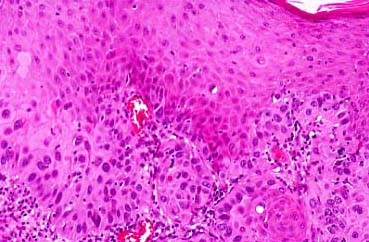

Squamous Cell Carcinoma = الكارسينوما شائكة الخلايا